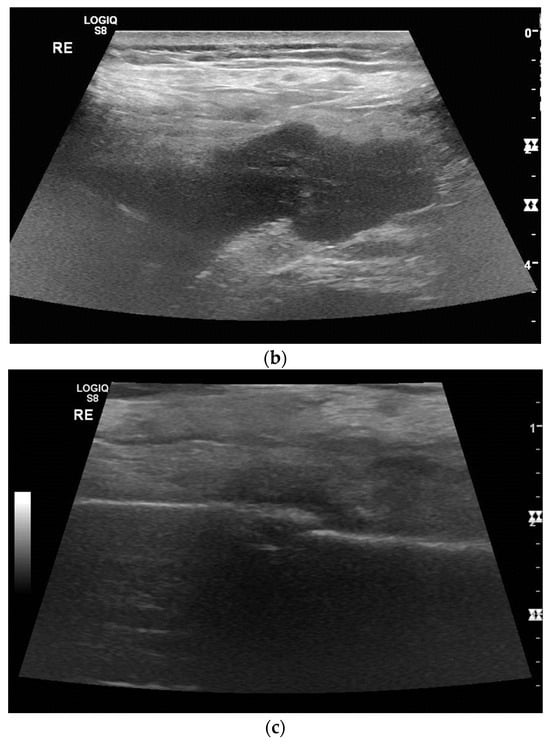

1. Introduction

2. Primary Pulmonary Sarcomas

3. Pleural Mesothelioma